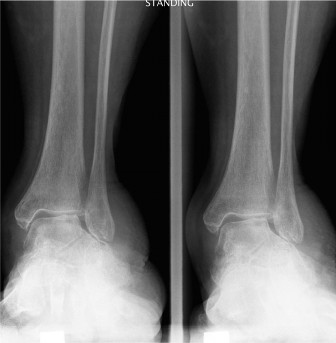

A 57-year-old female presents with an 8-month history of pain at the Achilles tendon insertion. She reports a…

A 65-year-old female with a history of osteopenia presents complaining of hindfoot pain for the past 2 years.…